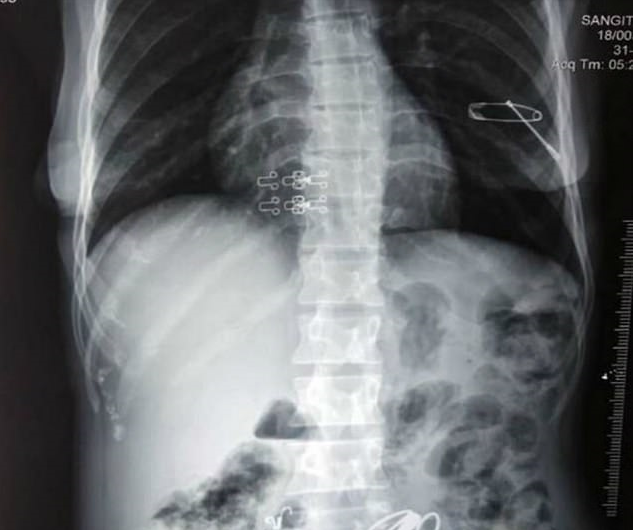

این اشیا شامل پیچ و مهرهها و جواهرات و سنجاق و طناب بود که در طی 3 ساعت جراحی از بدن این پیرزن خارج شد. تصاویر رادیوگرافی نشان میدهند که برخی از این اجسام نوک تیز به ریه این فرد نزدیک شده بودند.

یک پین نیز دیواره معده این زن هندی را سوراخ کرده بود که پزشکان را مجبور به جراحی اورژانسی کرد.